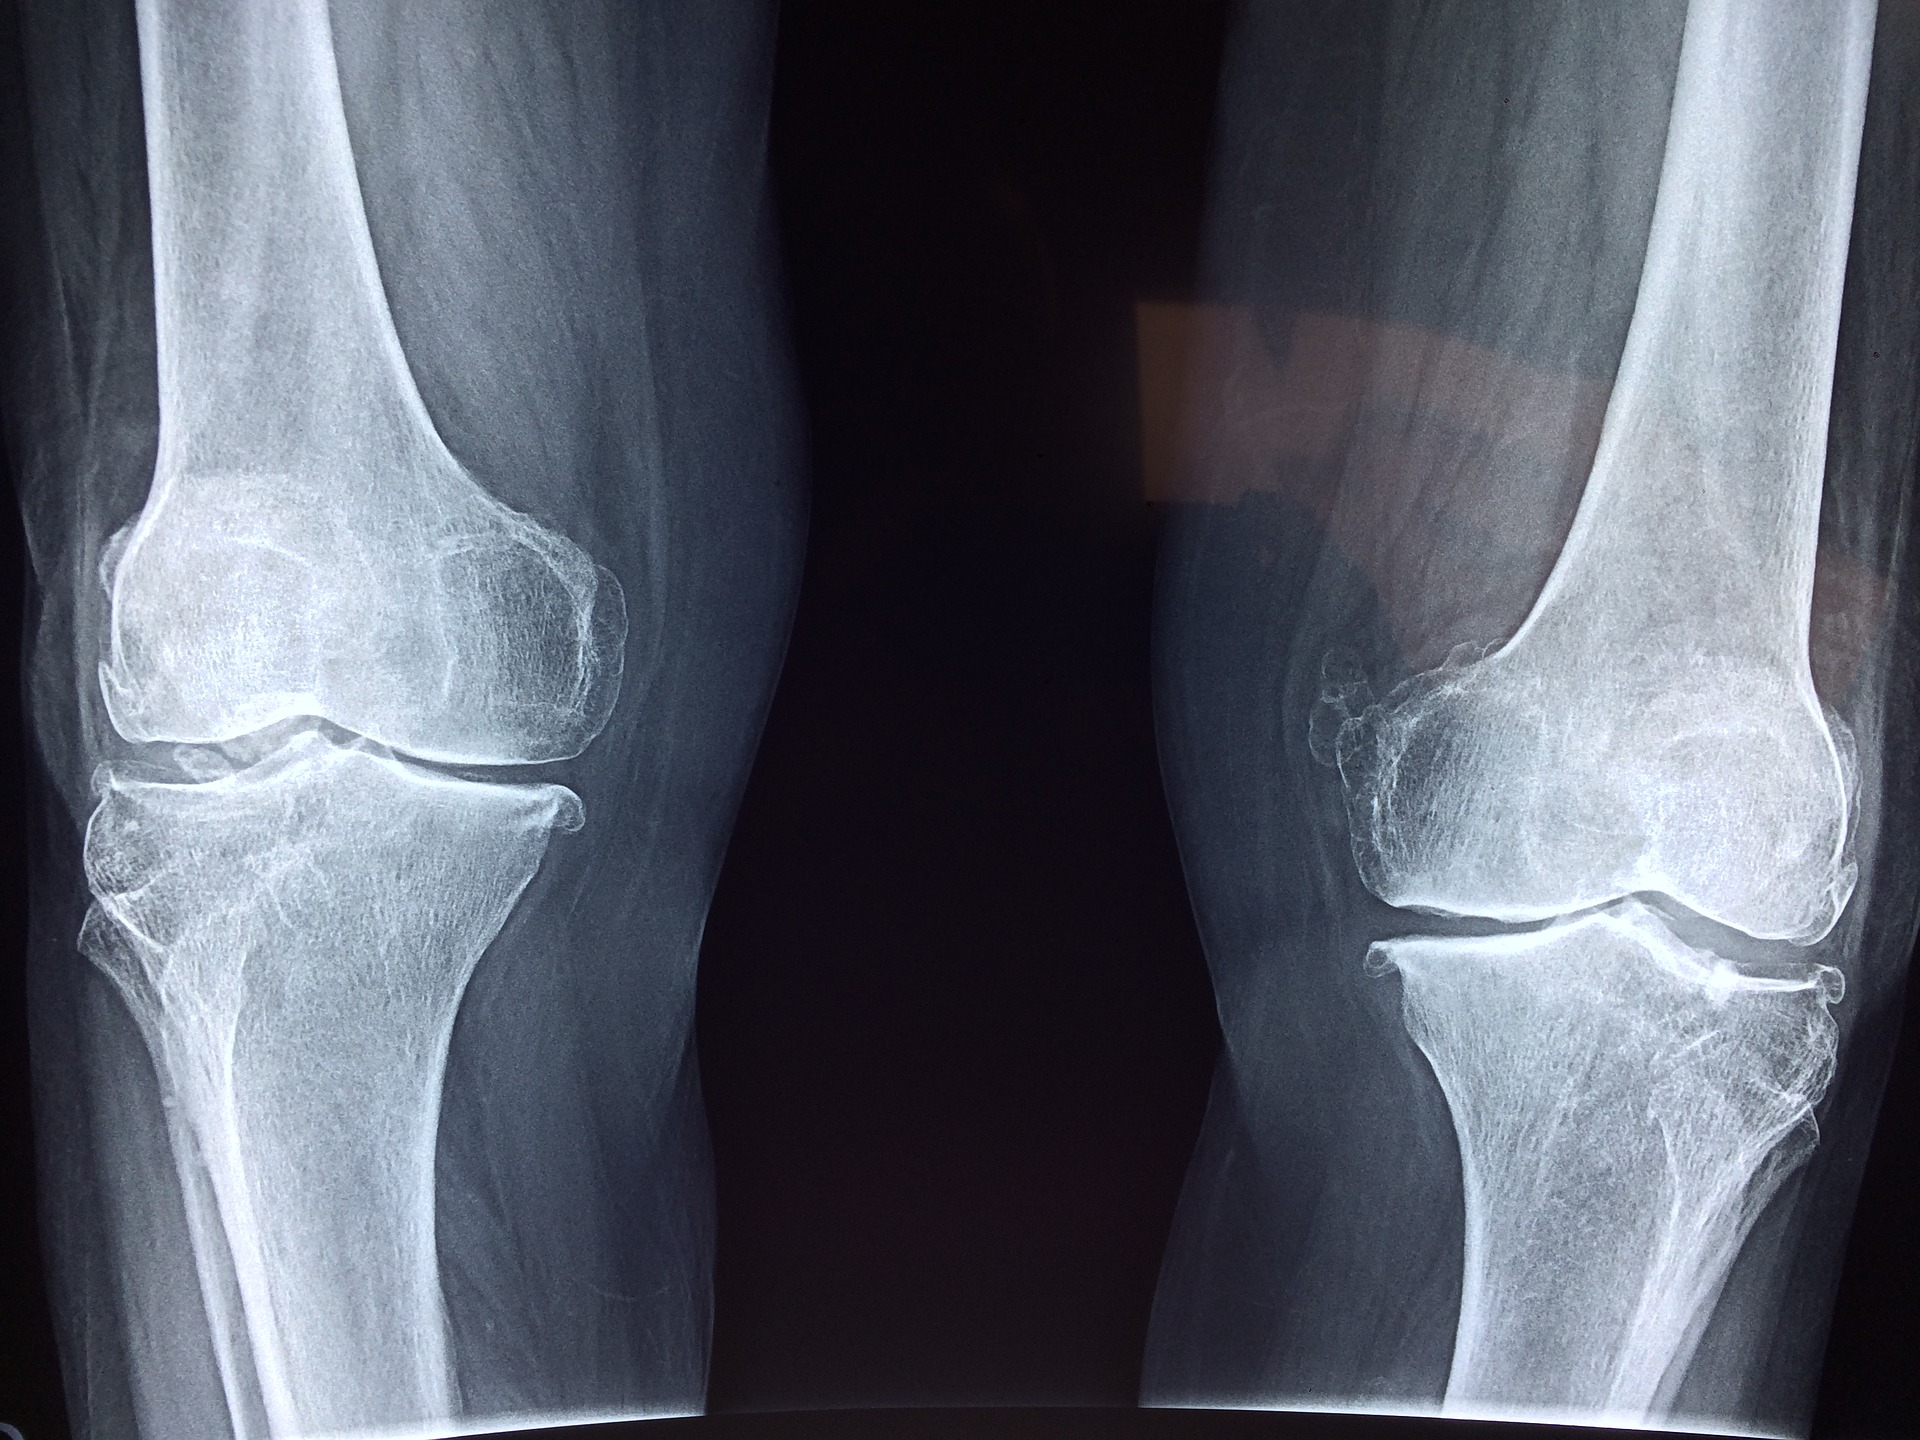

Wady rozwojowe są problemem dzisiejszego świata. Niektóre są mniej niektóre bardziej poważne. Musimy diagnozować je …

Dzisiaj coraz więcej spotyka nas różnych uszkodzeń ciała. Aktywne życie czy uprawianie sportu mogą postawić …

Wszelkiego rodzaju uszkodzenia ścięgien są bardzo wielkim problemem. Przydarzyć się to może zarówno sportowcom jak …